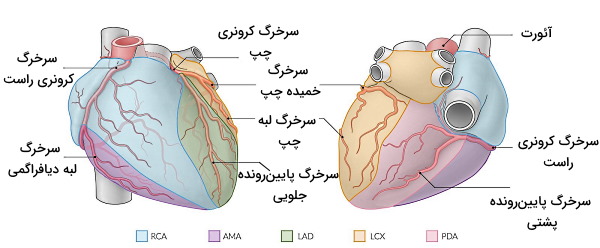

آناتومی رگ های کرونری

خونرسانی به بافتهای قلب وظیفه سرخرگهای کرونری است. این رگها از سینوس آئورت و بخش ابتدایی آئورت پایینرونده جدا میشوند و شاخههای فراوان آنها اکسیژن میوکارد قلب را فراهم میکند. سرخرگ کرونری راست و چپ دو شاخه اصلی خونرسانی به قلب هستند.

- سرخرگ کرونری راست: سرخرگ لبهای راست، سرخرگ پایینرونده پشتی، سرخرگ گره دهلیزی-بطنی و سرخرگ گره سینوسی-دهلیزی شاخههای سرخرگ کرونروی راست هستند. سرخرگ لبه راست (لبه دیافراگمی) خون دیواره بطن راست و نوک قلب، سرخرگ پایینرونده پشتی به یکسوم از سپتوم دهلیزی-بطنی، میوکارد نزدیک نوک قلب و میوکارد نزدیک ماهیچههای پاپیلری، سرخرگ گره دهیلزی-بطنی خون مورد نیاز این گره و رشتههای هیس و سرخرگ گره سینوسی، خون گره سینوسی را فراهم میکند.

- سرخرگ کرونری چپ: این سرخرگ به دو شاخه اصلی سرخرگ پایینرونده چپ و سرخرگ خمیده چپ تقسیم میشود. سرخرگ پایینرونده در سطح جلویی، بین بطن چپ و راست به سمت نوک قلب حرکت کرده و خون بخشی از دهلیز و بطن چپ (کمتر از نصف)، بخش جلویی بطن چپ، دوسوم جلویی سپتوم بین بطنی، بخشی از ماهیچههای پاپیلار و نوک بطن را تامین میکند. سرخرگ خمیده چپ در شیار کرونری سطح پشتی حرکت کرده و قبل از شیار بینبطنی پشتی تمام میشود.

خون این رگها پس از تبادل اکسیژن و مواد غذایی با بافت قلبی بهوسیله سینوس کرونری (سیاهرگ سطح پشتی قلب) از میوکارد به دهلیز راست منتقل میشود. سیروس کرونری خون با غلظت پایین اکسیژن را از چهار شاخه اصلی دریافت میکند.